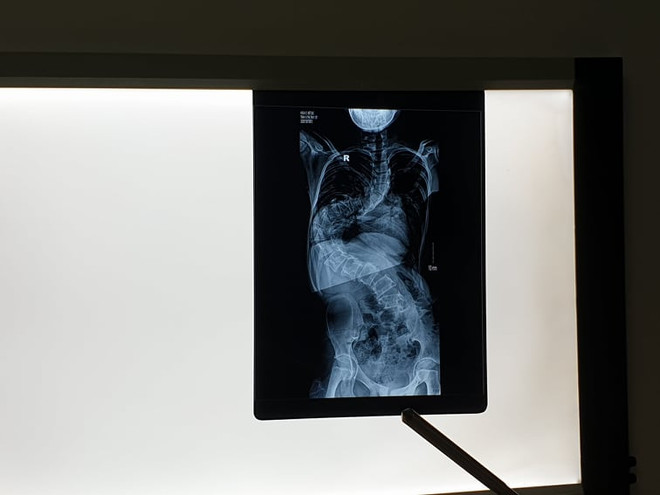

Hà Nội: Nữ bệnh nhân 13 tuổi cột sống uốn lượn như chữ S ảnh 1Hình ảnh trên phim chụp cho thấy cột sống của bệnh nhân uốn như chữ S. (Ảnh: PV/Vietnam+)

Bác sỹ Nguyễn Hoàng Long, Phó Trưởng khoa Phẫu thuật Cột sống (Bệnh viện Việt Đức) cho biết đây là trường hợp khá hiếm gặp, bị vẹo cột sống trong tình trạng rất nặng. Hình ảnh trên phim chụp cho thấy cột sống của bệnh nhân uốn như chữ S.

Bác sỹ Long phân tích bình thường các đốt sống của mọi người xếp chồng lên nhau theo đường thẳng đứng nhưng đường cong của bệnh nhi trên rất lớn, giống hình chữ S, ngoài ra đốt sống nằm sát vào thành ngực thay vì nằm giữa cơ thể.

Bệnh nhân được chẩn đoán có góc cột sống vẹo tới 150 độ, cần phải phẫu thuật để tránh những nguy cơ cho sức khoẻ. Khi tình trạng vẹo cột sống từ 100 độ trở lên sẽ ảnh hưởng đến chức năng của tim và phổi, làm dung tích phổi bé lại, thở khó khăn khăn và ảnh hưởng đến các tạng trong ổ bụng. Do đó trong mổ bệnh nhân có thể gặp các nguy cơ do tạng hoặc động mạch chủ bị kéo căng... Nữ bệnh nhân trên sau phẫu thuật phải mất thời gian dài để phục hồi chức năng.